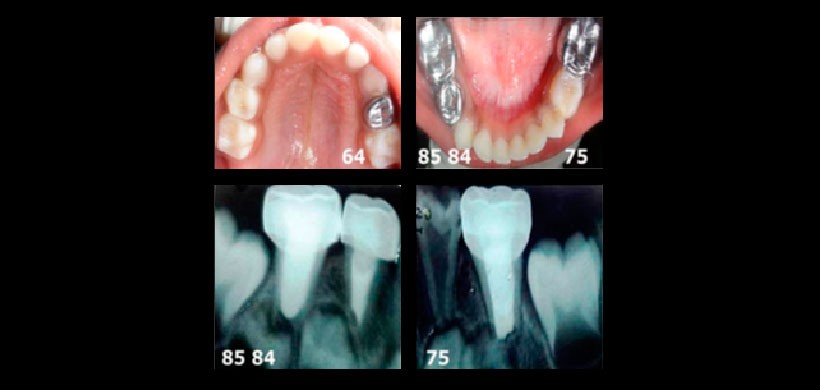

Figura 2: Radiografías periapicales preoperatorias de un paciente pediatrico de 3 años de edad. Se realizó el examen radiográfico por presencia de múltiples lesiones de caries.